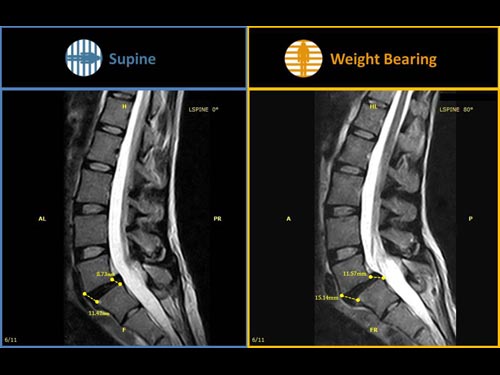

Nová končetinová magnetická rezonance G-scan Brio od společnosti Esaote je tomografický systém MRI, který umožňuje studium všech kloubů i páteře, ať už v klinostatické (vleže) nebo ortostatické (vážící) poloze, protože magnet i pacient se mohou otáčet od 0 do 90 stupňů. Díky inovativnímu designu G-scan mohou být pacienti Brio skenováni v poloze nesoucí váhu, aby se usnadnila diagnostika MSK u těch patologií, které se mohou měnit v důsledku držení těla a polohy, jako jsou bolesti dolní části zad.

• Váhové ložisko: poloha pacienta se stává nedílnou součástí výsledku vyšetření

• Další diagnostické schopnosti: jelikož gravitační síla generuje bio-mechanické změny v anatomii, MR zobrazení v přirozené poloze ve stoje vám umožňuje dosáhnout důležitých dalších informací ve srovnání s tradičními MRI

G-scan Brio je speciálně navržen pro všechny aplikace pohybového aparátu. Otevřený a naklápěcí design je nový a inovativní způsob provádění MRI, při kterém se poloha pacienta stává nedílnou součástí výsledku vyšetření. G-scan Brio poskytuje pacientovi vysoký komfort s funkcí nejnovějšího zobrazovacího výkonu a sekvencí společnosti Esaote.